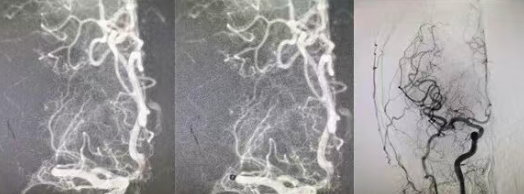

国文医院为颅内血肿患者成功实施双侧硬脑膜下切开引流术

​突发肢体活动不灵,极易被误认为脑梗死,若误诊误治可能延误病情甚至危及生命。近日,国文医院神经外科凭借精准诊断与精湛手术技术,成功为一名60岁硬膜下血肿患者实施双侧硬脑膜下切开引流术,以高效、规范的救治方案帮助患者转危为安,充分彰显了医院在颅脑重症诊疗领域的硬核技术实力。 阅读量:145